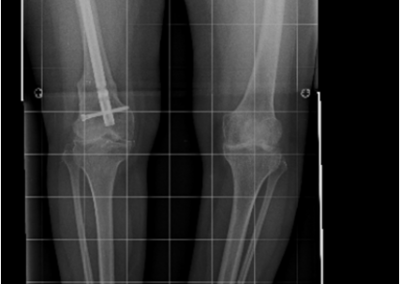

arthritis deformity surgery endoprosthesis hip prosthesis ilizarov ilizarov surgery infected nonunion knee prosthesis lengthening surgery limb lengthening surgery nonunion periprosthetic infection psodoartroz revision surgery total hip prosthesis total knee prosthesis